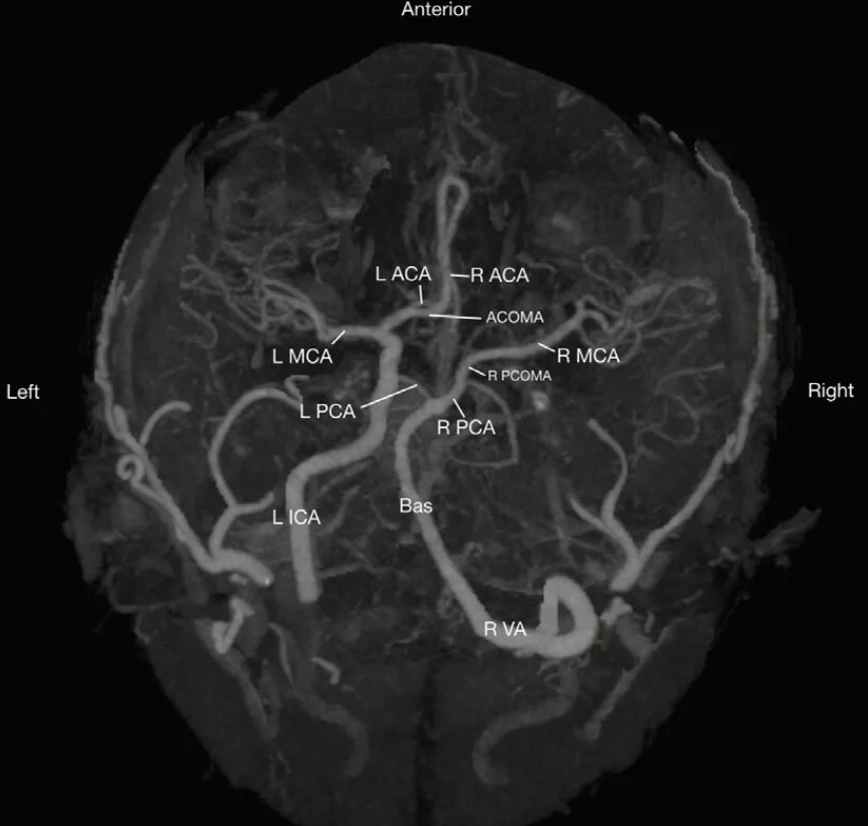

Label the circle of willis

Please label the circle of willis